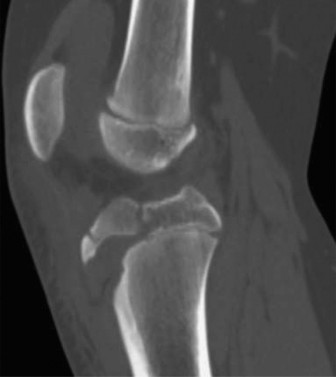

The initial anteroposterior (AP) and lateral radiographs of the right femur demonstrate a complete, displaced, length-stable transverse fracture of the middle third of the femoral diaphysis. There is minimal comminution. The traction splint has effectively restored length, though there remains slight apex-lateral and apex-anterior angulation.

Crucially, dedicated AP and lateral views of the right hip and right knee are obtained. The femoral neck is intact, with no evidence of a basicervical or transcervical fracture—a classic "missed injury" in the setting of high-energy femoral shaft fractures. The distal femoral physis is open and symmetric, with no widening or displacement to suggest a concurrent Salter-Harris injury.

Instead, the diagnostic focus shifts to meticulous radiographic templating. The narrowest portion of the medullary canal (the isthmus) is measured on both the AP and lateral projections. The fundamental rule for Elastic Stable Intramedullary Nailing (ESIN) dictates that the combined diameter of the two selected nails should fill approximately 80% of the narrowest diameter of the medullary canal. Therefore, the formula used is:

In this patient, the isthmus measures 10 mm. Thus, two 4.0 mm titanium elastic nails will be selected to provide optimal biomechanical stability.

- Protecting the Physis: Under direct fluoroscopic guidance, the starting points are localized. It is absolutely critical to stay strictly proximal to the perichondrial ring and the distal femoral physis to prevent iatrogenic growth arrest.